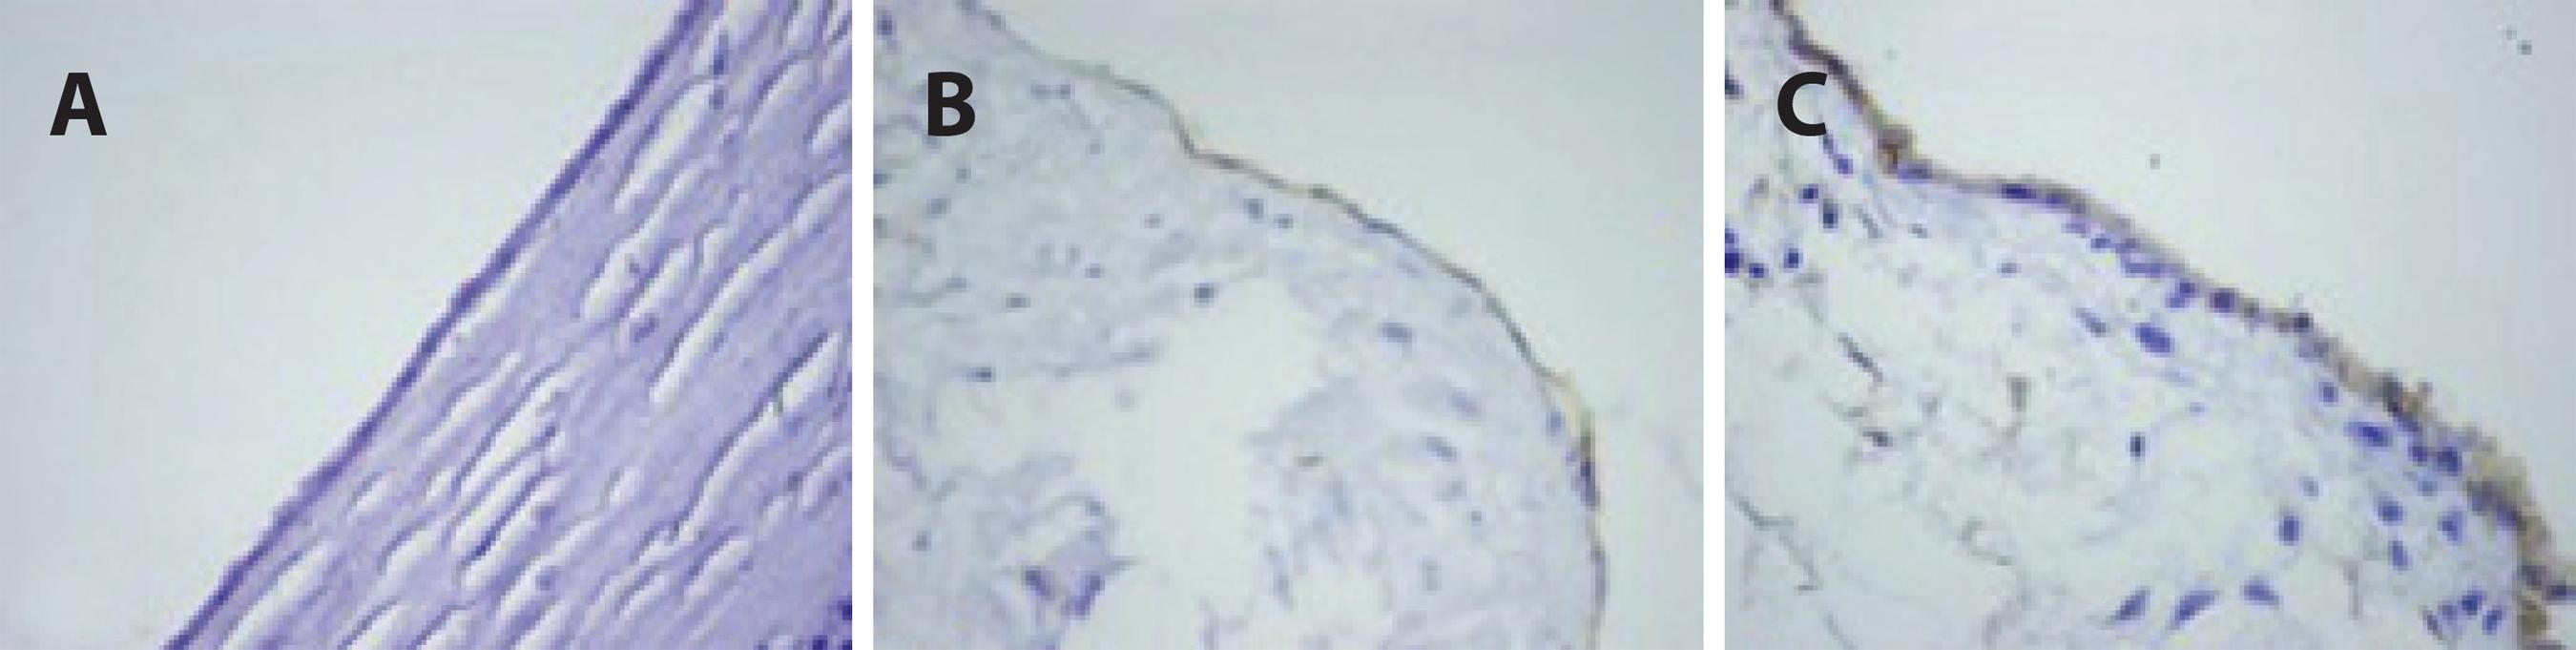

The TAS, TOS and OSI levels of the blood samples and corneal tissues are presented in tables 1 and 2. The TAS, TOS and OSI levels in the blood samples were not significantly different among the groups (p>0.05 for all). The OSI levels in corneal tissue were significantly different in the TB group compared with the sham and control groups (p<0.05 for all); however, no significant difference was found between the control and sham groups (p>0.05 for all). Additionally, immunohistochemical staining for caspase-3 and -8 showed higher apoptotic activity in the TB group than in the sham and control groups (Tables 3 and 4; Figures 1 and 2).

The samples were fixed with 10% formaldehyde and 4 µm thick specimens obtained from paraffin blocks were stained using a standard streptavidin-biotin immunoperoxidase method with anti-caspase-3 (cleaved) (Clone: N/A, Catalog No: PP 229 AA, Biocare Medical) and -caspase-8 antibodies (Clone: C502S, Catalog No: GTX59555, Gene Tex). Tonsillar tissue was used as a positive control, and all specimens were evaluated using light microscopy (Olympus BX51TF, Olympus Corporation, Tokyo, Japan). Also, immunohistochemical staining was evaluated semi-quantitatively using a scale from 0 to 3, on which negative staining was rated 0, weak staining was rated 1, moderate staining was rated 2 and intense staining was rated 3.

Table 3 Immunohistochemical staining for caspase-3

| 0 | + | ++ | +++ | Total | |

|---|---|---|---|---|---|

| Sham group | 9 | 1 | - | - | 10 |

| Control group | 7 | 1 | - | - | 8 |

| Trypan blue group | 4 | 4 | 1 | - | 9 |

Table 4 Immunohistochemical staining for caspase-8

| Control group | 6 | 2 | - | - | 8 |

| Trypan blue group | 3 | 4 | 2 | - | 9 |